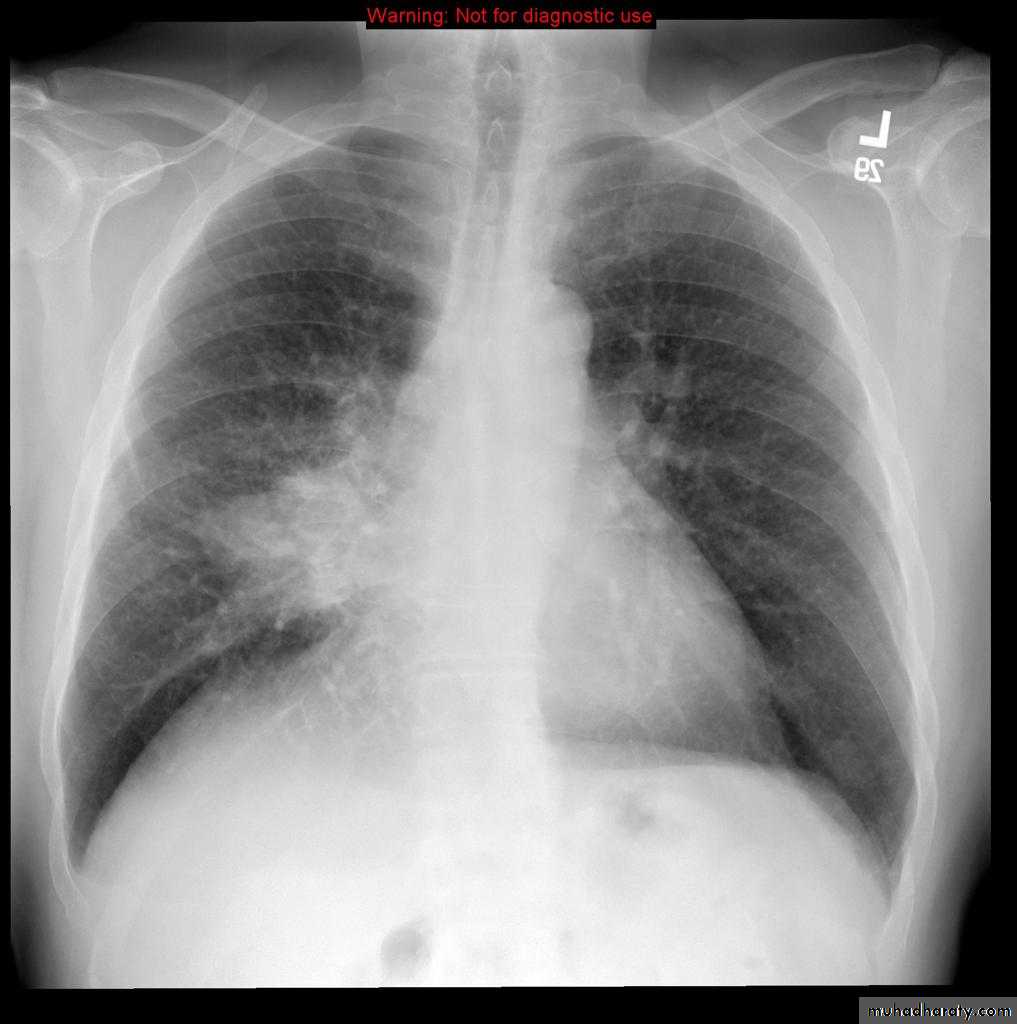

4. Miliary tuberculosis is uncommon but carries a poor prognosis. It represents haematogenous dissemination of an uncontrolled tuberculous infection. It is seen both in primary and post-primary tuberculosis. Although implants are seen throughout the body, the lungs are usually the easiest location to the image. Miliary deposits appear as 1-3 mm diameter nodules . are uniform in size and uniformly distributed